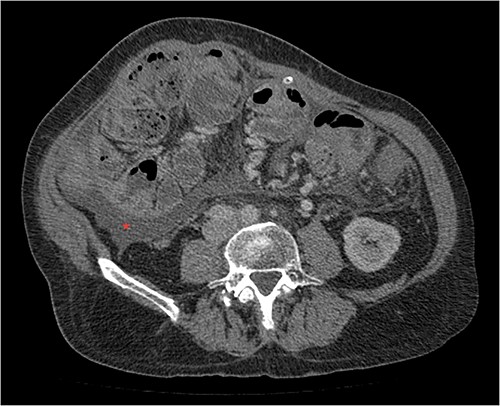

His clinical history and contrast-enhanced computed tomography (CT) findings (Figs 1–3) were compatible with EPS in Stage 4 (Table 2). Laboratory tests were non-specific, showing inflammation and malnutrition. He underwent nutritional support, corticosteroids and surgery. In surgery, fibrocollagenous membrane resection and enterolysis were done. Postoperative period was complicated by pneumonia treated with piperacillin+tazobactam and later bacterial peritonitis treated with ertapenem. The patient was discharged after 29 days with adequate nutrition and asymptomatic.

Portal phase transversal section image on CT showing membrane-like structure and loculated ascites (asterisk).

Imaging exams, mainly CT are important to evaluate causes of bowel obstruction [4]. Dilated or non-dilated small intestine loops may be wrapped in a membrane-like structure, proximal bowel dilatation, thickened peritoneum with diffuse or local calcification, and loculated ascites are some of the findings on CT [1, 12]. Barium X-ray provides a clue to bowel encapsulation, showing clustered loops of the small intestine in the center of the abdomen, known as the cauliflower sign [4]. Ultrasound and magnetic resonance imaging may give a clue but are rarely used [1, 12].